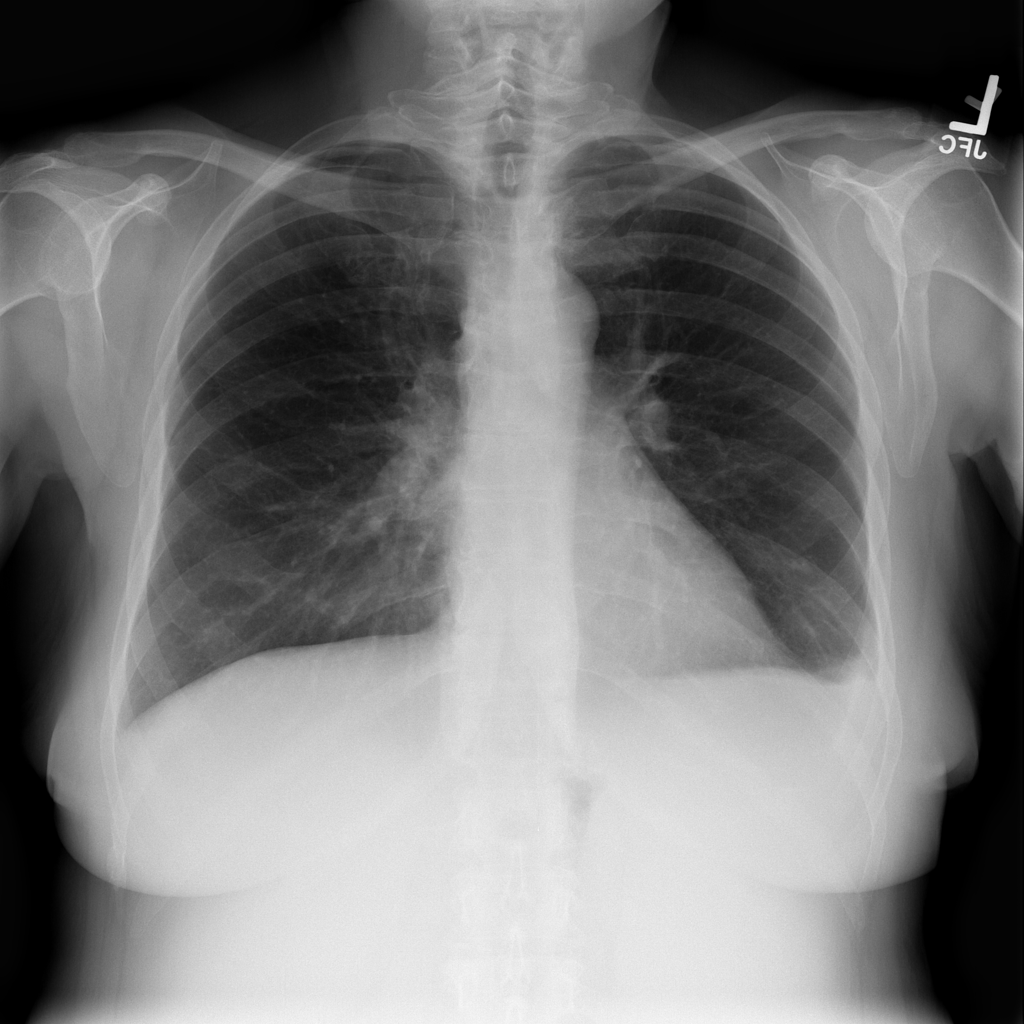

PAT-40F9 · IMG-004Effusion

PAT-40F9 · IMG-004

PA